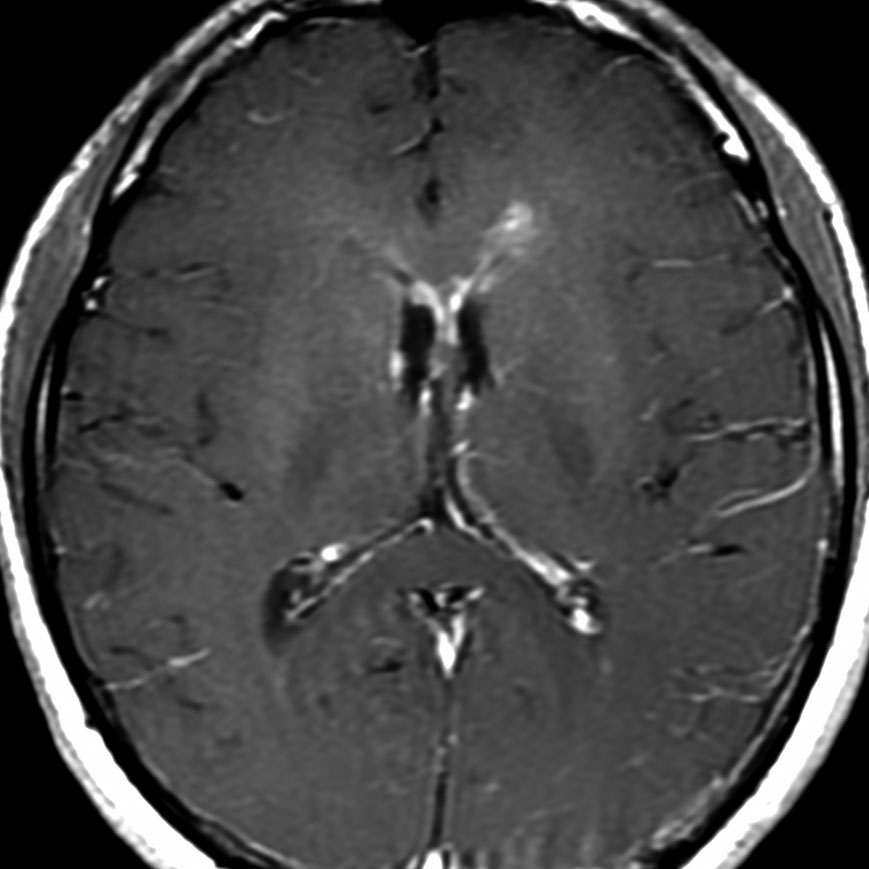

左はICE化学療法 (IFO/CDDP/VP-16)前,右は1コース終了後です。腫瘍は顕著に縮小してgerminomaとして普通の化学療法反応性を示します。また,松果体と下垂体には腫瘍はありません。